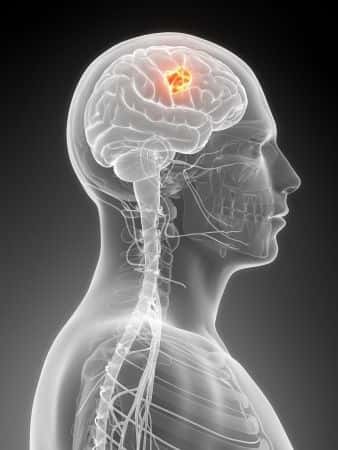

This case involves a thirty-year-old woman who presented to the urgent care clinic with headaches. She was prescribed pain medications and discharged home. Two days later, she presented to the emergency department with the same chief complaint. A CT scan with contrast was ordered which revealed a mass in the posterior fossa. Neurosurgery was consulted, and the patient was transferred to a nearby hospital. The decision was made by the hospitalist and neurosurgeon to wait to perform an awake brain surgery procedure the following day, but the patient died that evening. The plaintiff alleged that mismanagement caused deterioration of this patient until she expired.

Most likely the patient herniated from the increased pressure and died from this. I think that the CT scan results and specific signs of increased Intracerebral pressure through info on physical exam, CT results, clinical picture, vomiting presence, etc. would be critical pieces of information to further determine this patient's condition state and appropriate management. Brain stem herniation is most likely the cause of death. Prompt management and excision of the mass to relieve the pressure on the brain stem, thus preventing mortality.